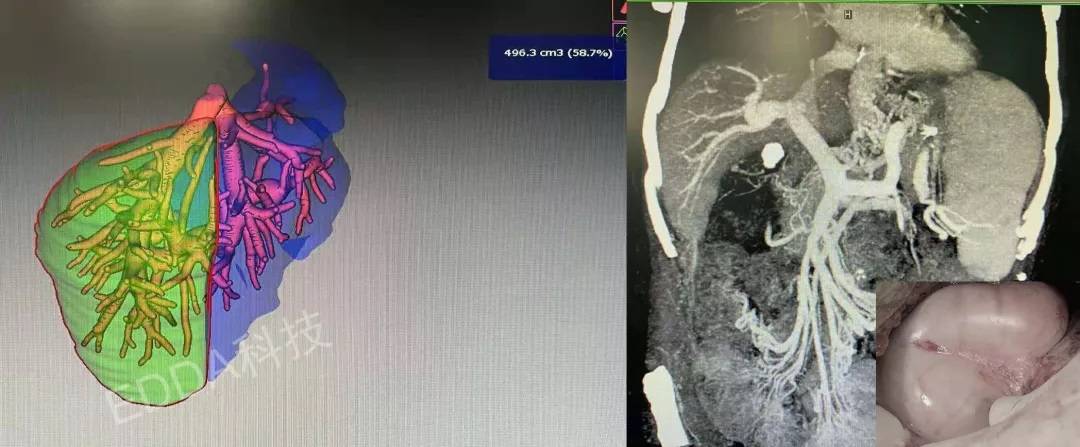

患者177cm、85kg,其子31岁,187cm、92kg,紧急医学评估及伦理审查,发现供者门脉三型,胆道右后叶支汇入左肝管,左半肝仅占全肝26%,右后叶评估690cm3,GRWR大于0.8%,剩余左三肝60%,由其子捐献右后叶肝脏行急症活体肝移植手术,手术过程顺利。